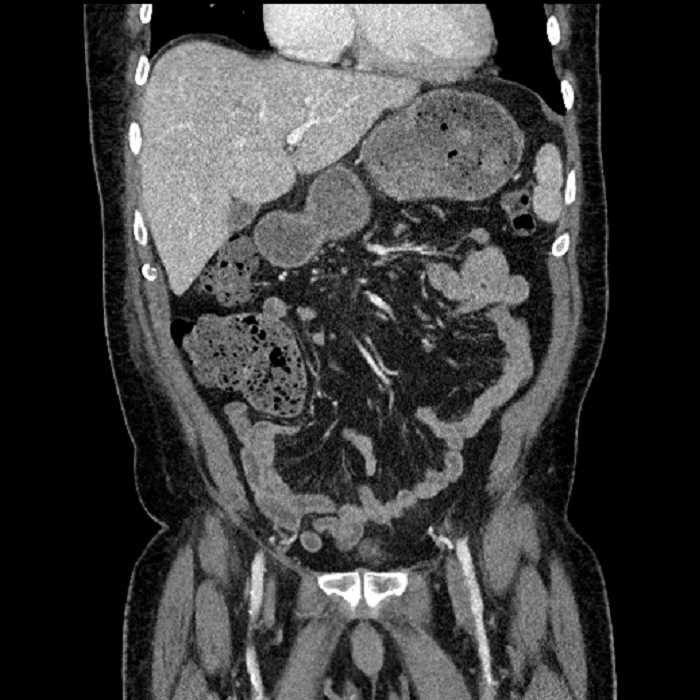

• Large fluid density structure in hepatic segments 7 and 8 measuring 10 x 7 x 7 cm with internal septation and circumferential ill-defined low density compatible with edema

• Peripherally enhancing subcapsular collections along the anterior margin of the left hepatic lobe measuring 3 x 1 cm and 2 x 1 cm

• Clearly marginated fluid density structure in segment 7 and several other scattered tiny hypodensities, which likely represent cysts

• Hepatic abscess

Acute sigmoid diverticulitis complicated by a small contained perforation and a large abscess in the right hepatic lobe. Additional small subcapsular abscesses along the anterior margin of the left hepatic lobe.

Additionally, loss of the normal fat plane between the peridiverticular collection and adjacent thickened loops of small bowel raises the potential for an enterocolonic fistula.

Hepatic abscess showing the double target sign with low density internally surrounded by a thin inner enhancing rim (red arrow) and ill-defined outer low density rim (yellow arrow). Blue arrow indicates an internal septation. Red arrows: additional smaller subcapsular abscesses. Red arrow: focal contained perforation associated with diverticulitis.